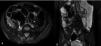

Enterografía por resonancia magnética, Secuencia BTFE: A) Corte axial, B) Corte coronal. Engrosamiento severo y edema parietal de aspecto estratificado del íleon terminal (cabezas de flecha) con un grosor de hasta 20mm y longitud de 10cm que condiciona estrechamiento luminal (flecha) con un porcentaje de estenosis del 98%, asociado a edema de la grasa mesentérica. Se realiza medición del Score Global MaRIA sumando las puntuaciones individuales de los seis segmentos (recto, colon sigmoide, colon descendente, colon transverso, colon ascendente e íleon) obteniéndose una puntuación global de 3 puntos.